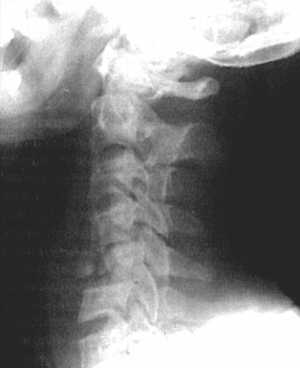

Рис. 3.5: а - травматический вывих С5-С6 позвонков;

б - межтеловая стабилизации металлическим цилиндром сразу после операции;

в - через 3 года после операции. |